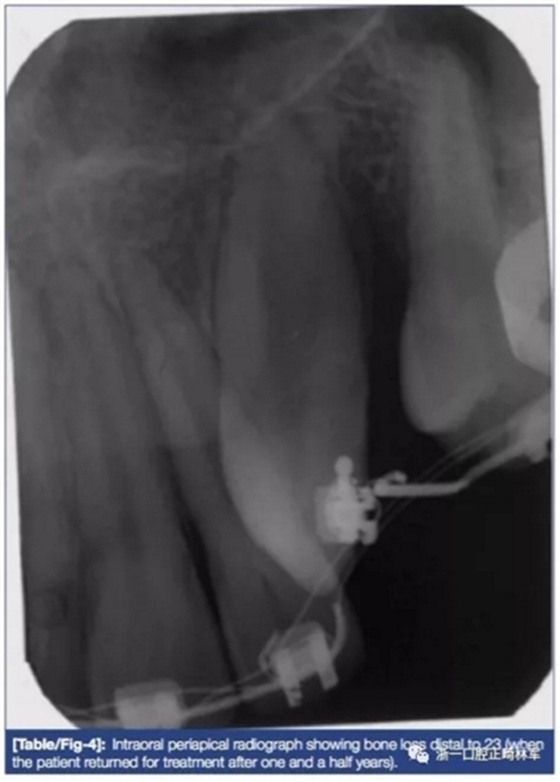

拍攝X片后提示23遠(yuǎn)中較大骨缺損(圖4)。為加快時(shí)間同時(shí)增加骨量,計(jì)劃形PAOO手術(shù)并植入干燥骨粉(FBDA)(圖5)。術(shù)后予3天500mg阿莫西林及1日止痛藥(500mg對乙酰氨基酚每日兩次)。